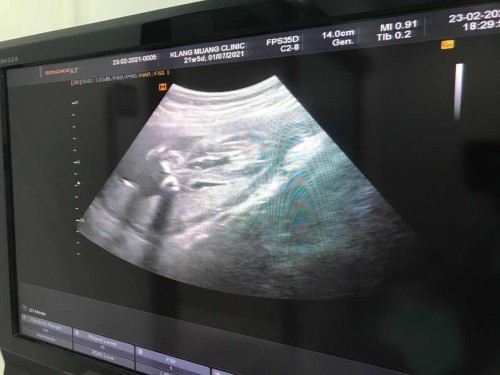

แม่ ๆ เห็นเป็นหญิง หรือชายคะ ☺️❤️🙏🏻

ผู้หญิงค่ะ เป็นกรีบเลยค่ะเเม่🥰

น่าจะหญิงนะคะ

ผู้หญิงค่ะ

ผู้หญิงคะ